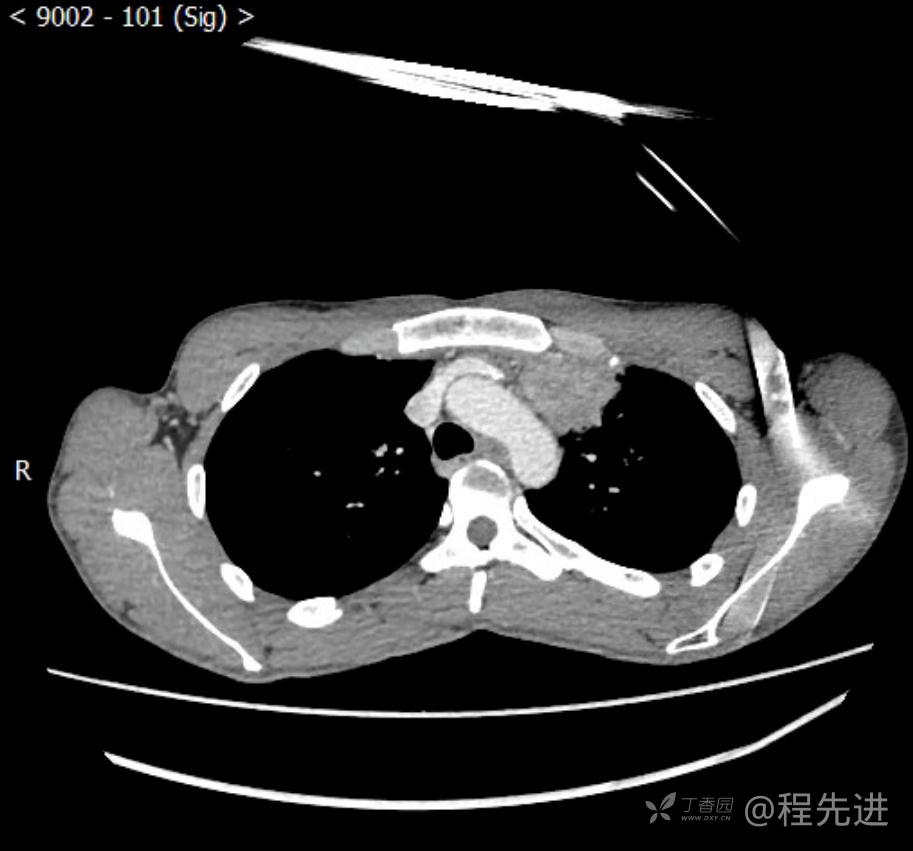

主诉:反复咳嗽1月,发现“纵隔”占位半月,乏力10余天。

现病史:患者1月前无明显诱因出现咳嗽,以夜间为著,伴有少量白痰,无发热,无胸痛、咯血,无痰中带血,未予重视,半月前外院行胸部CT检查发现“左前上纵隔”占位,未予进一步检查及治疗。近10余天自觉乏力,逐渐加重。